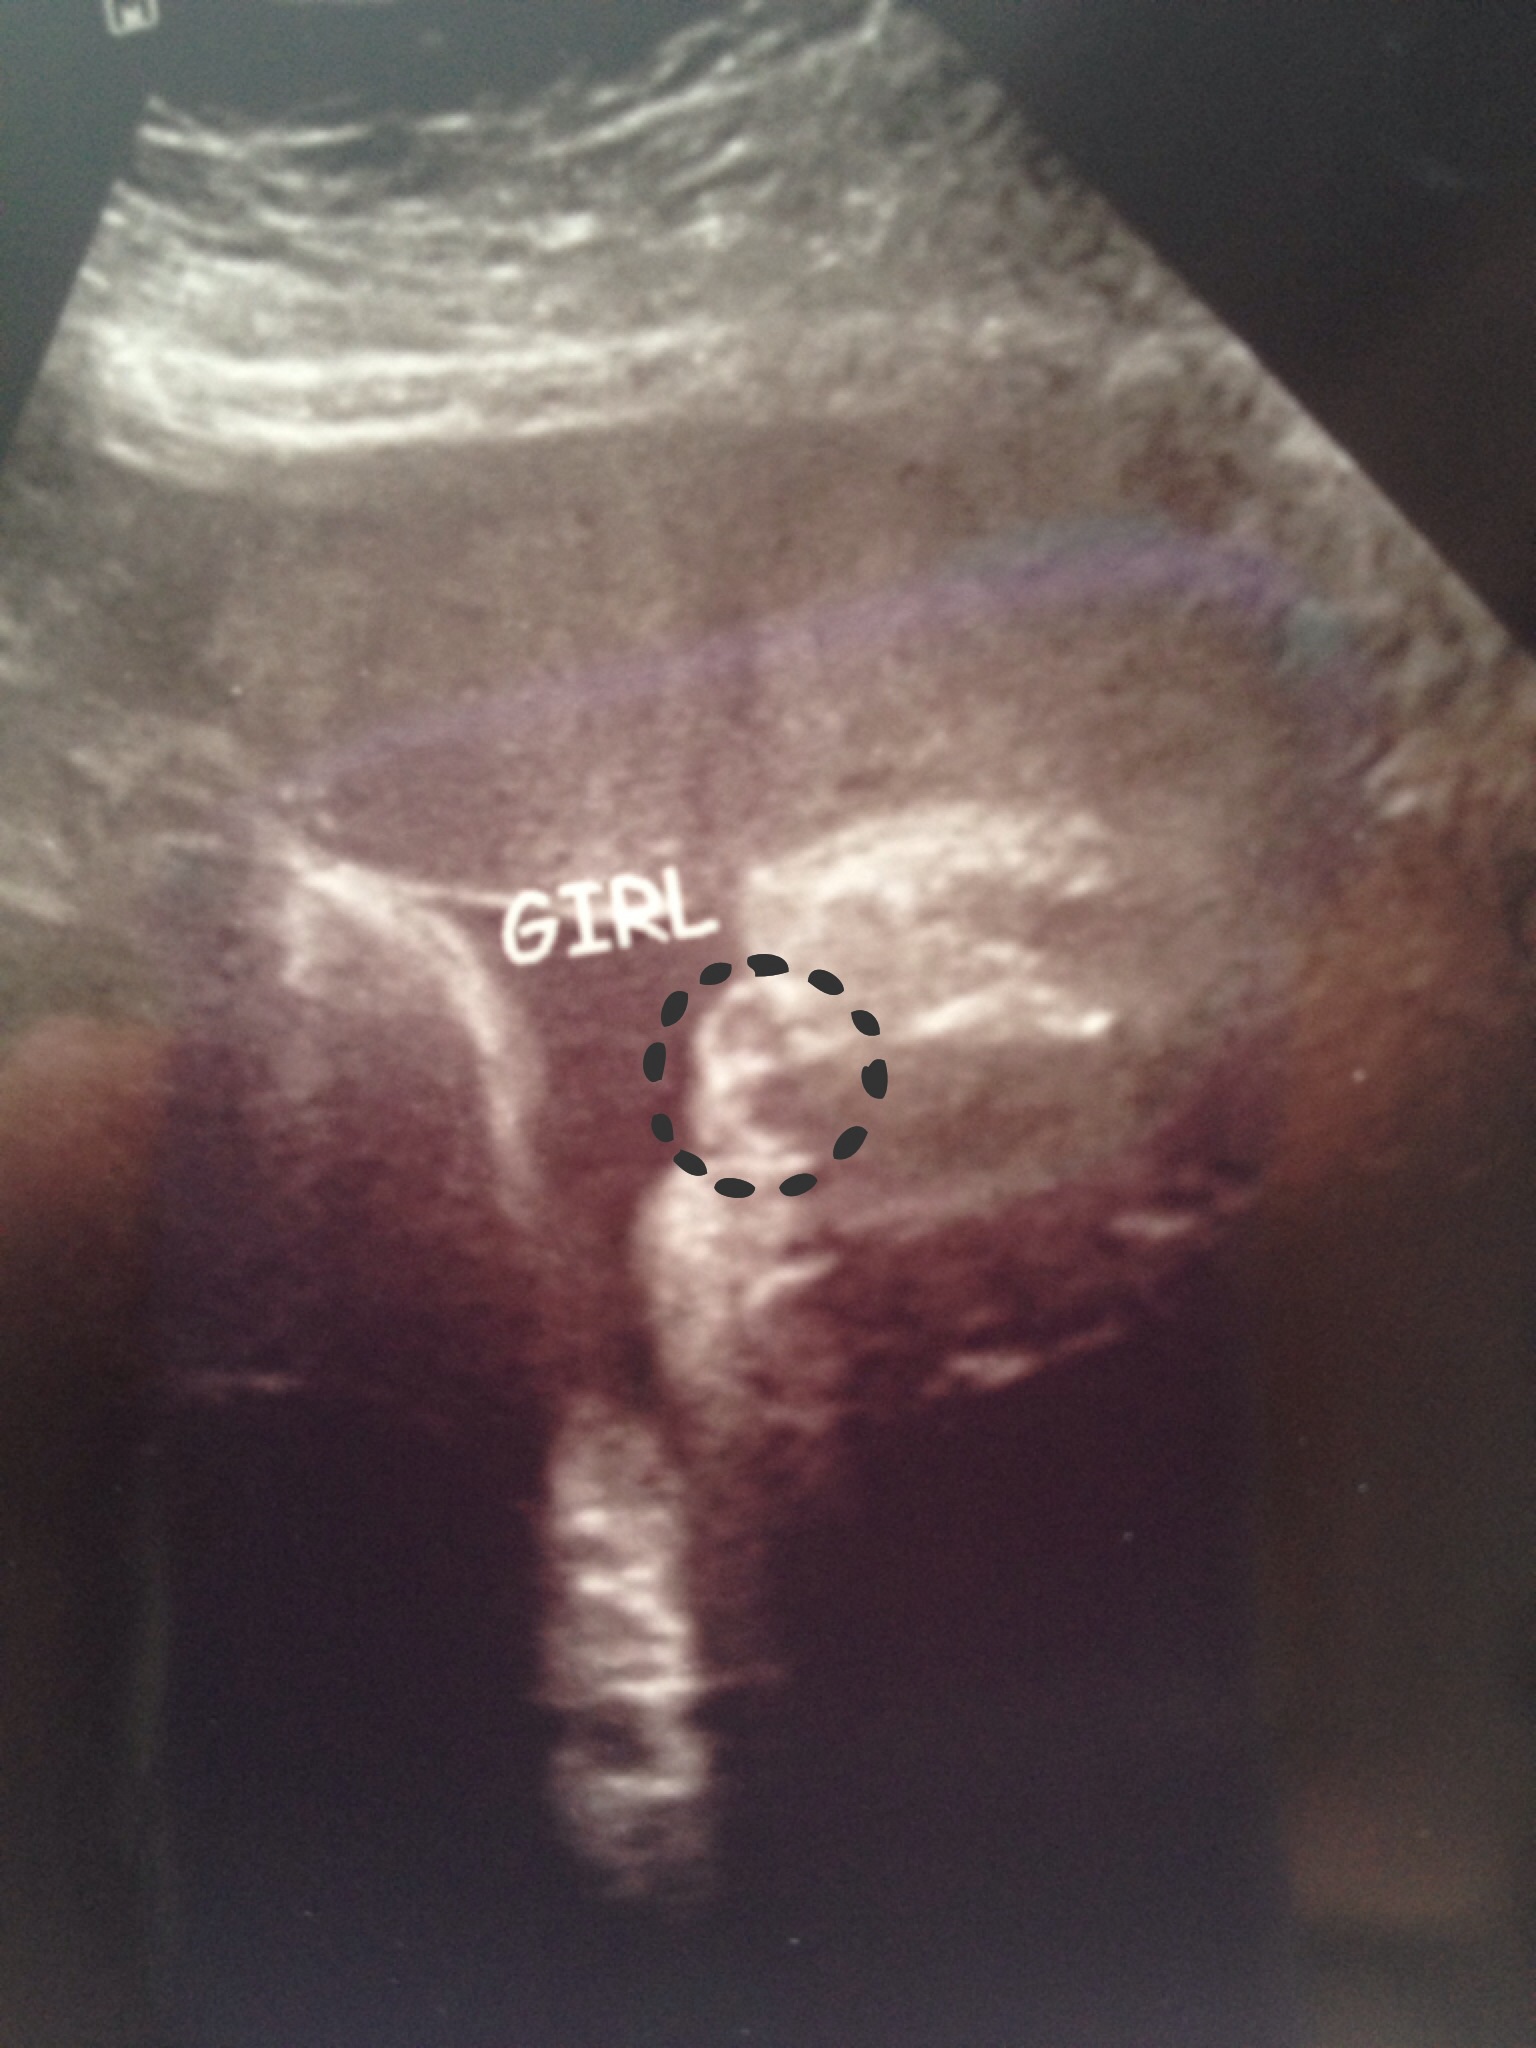

I have had two u/s confirm girl. I then had an appt with a specialist yesterday. They did u/s there & the girl asked what I was told I'm having. I told her girl. She then said "hmmm....looks like maybe girl." And then "could be swollen labia?" So now I'm three weeks away from delivery and I'm freaking out. Which is is? Swollen labia or a sac?! I have all pink things now!!Attachment 16434